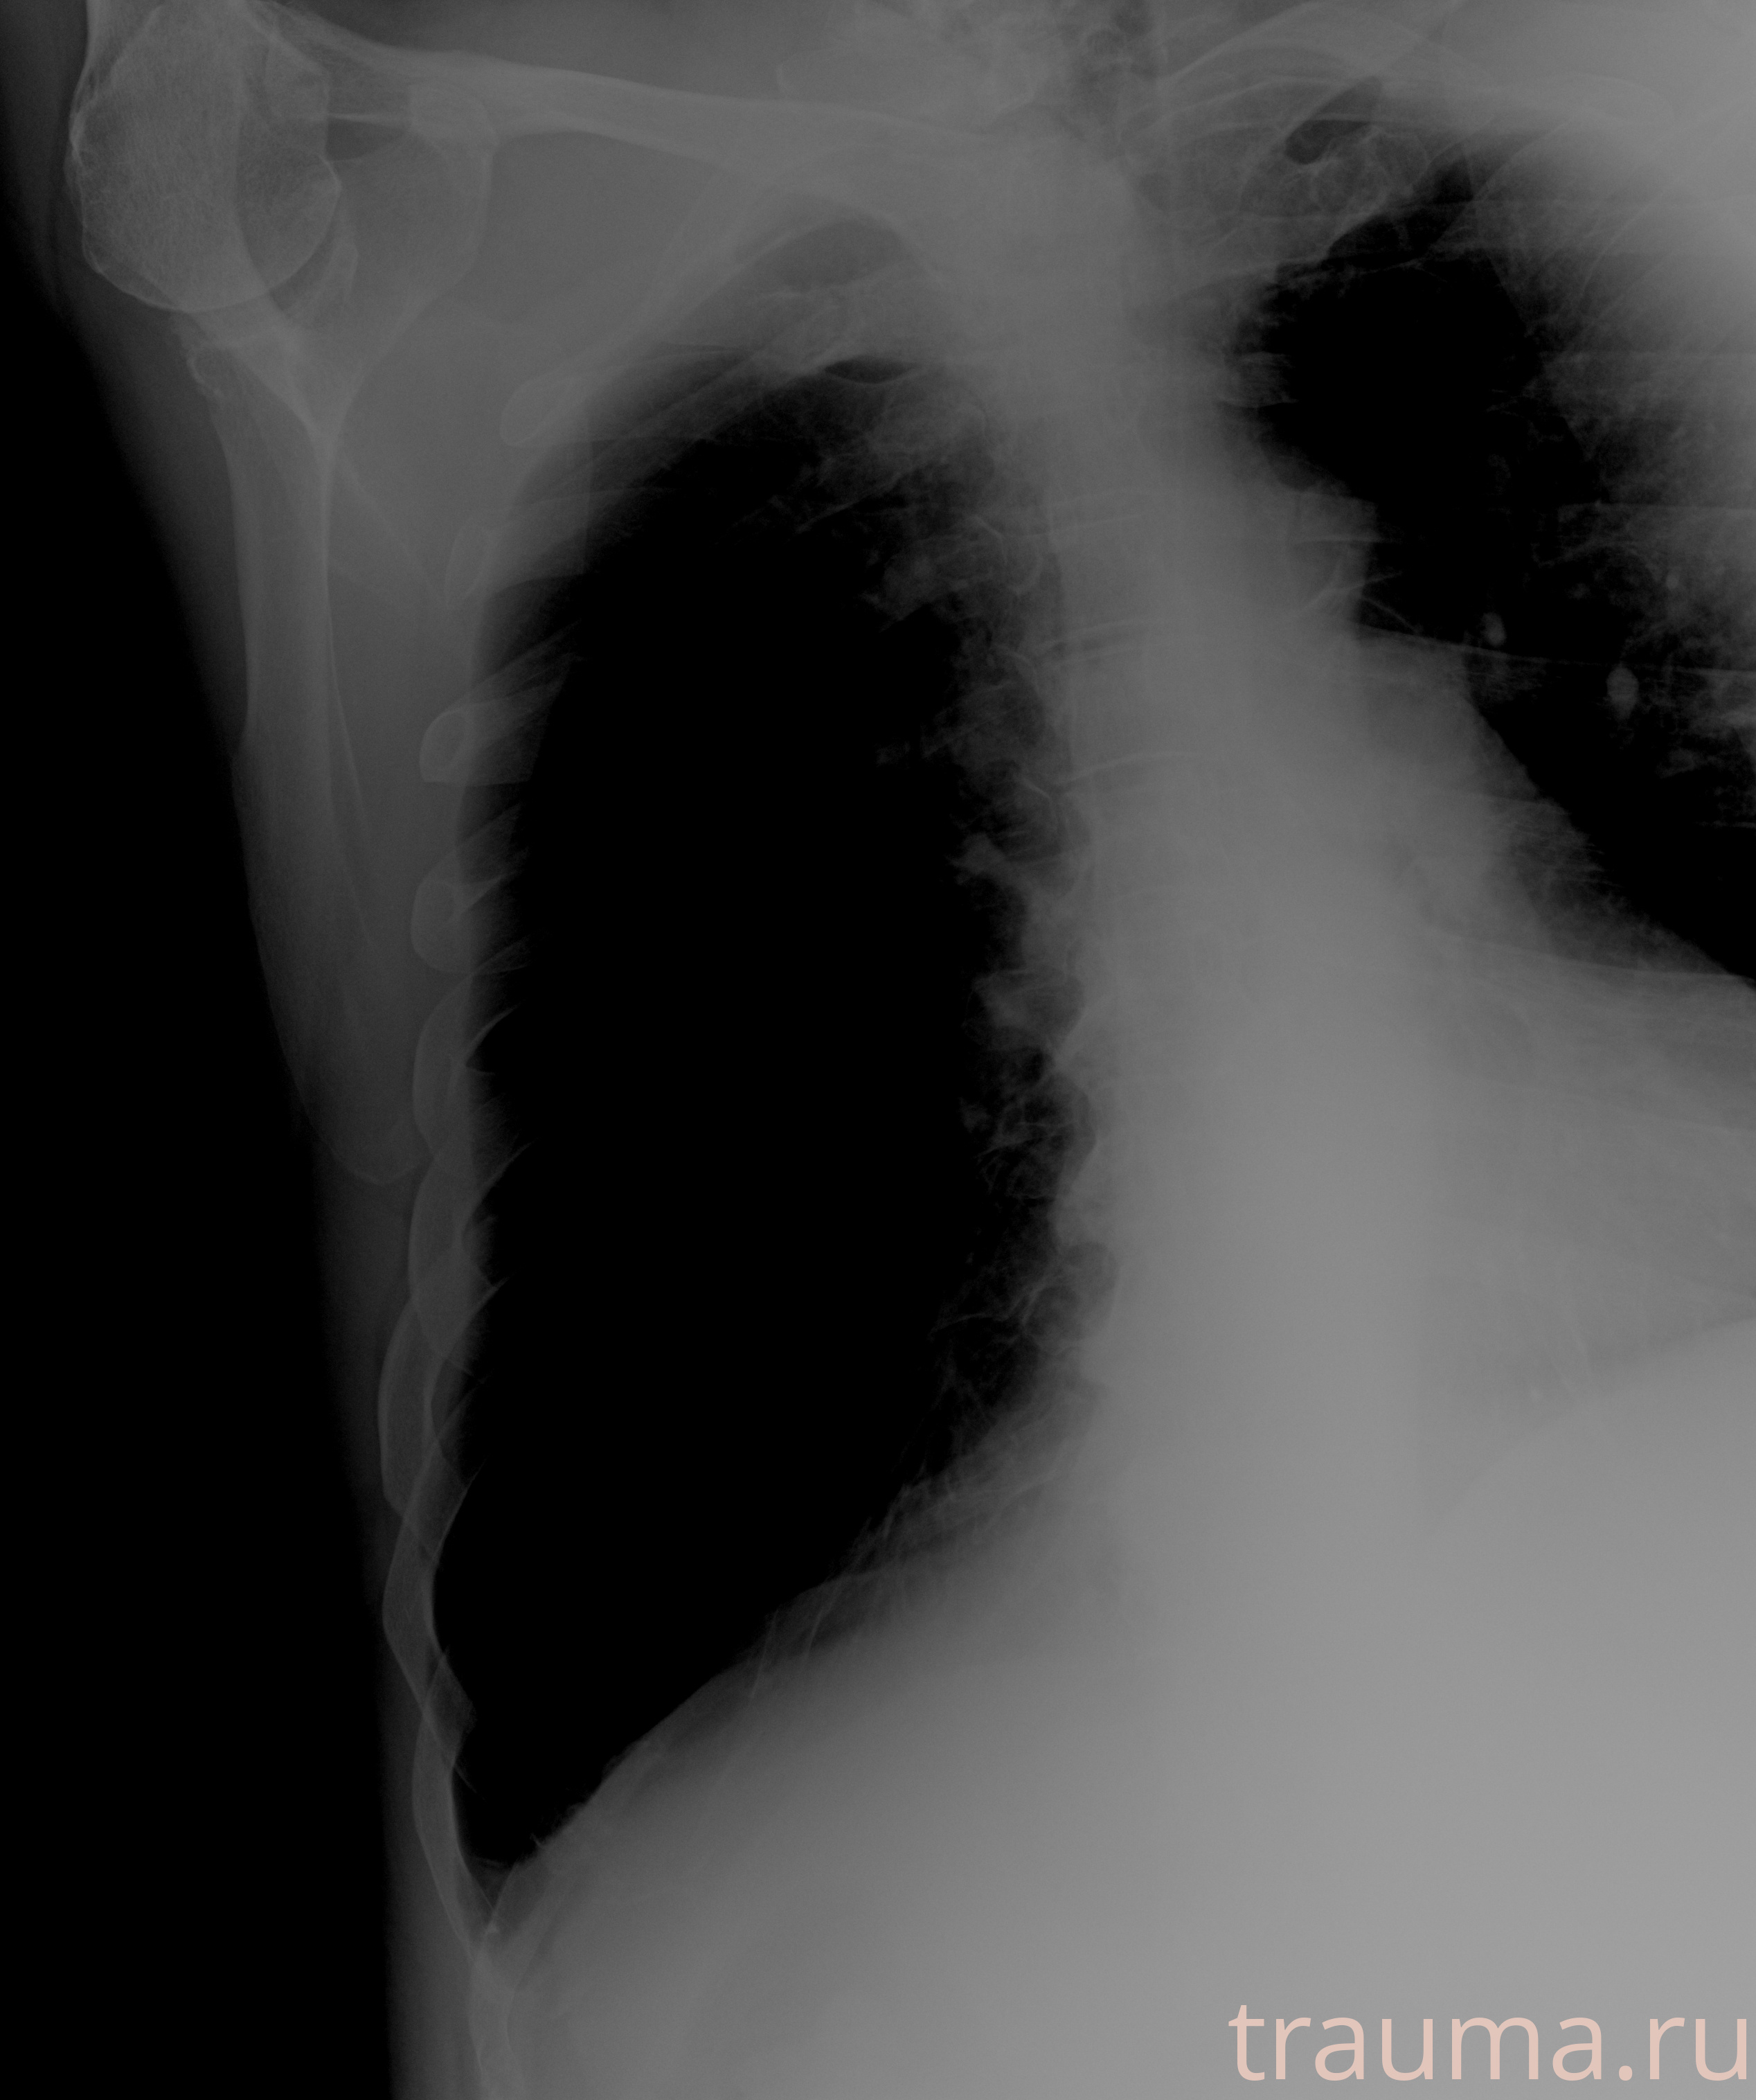

Рентгенограммы

Рентген на дому: по вашему адресу приезжает врач-рентгенолог, травматолог-ортопед с мобильным рентгеновским аппаратом, проводит диагностику травмы или заболевания, делает необходимые рентгенограммы, дает рекомендации по дальнейшему лечению. Получить качественные снимки в домашних условиях возможно благодаря уникальной методике, разработанной МосРентген Центром для института  Склифосовского